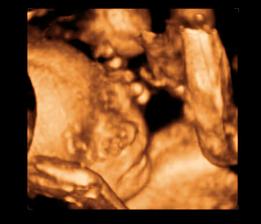

26 tt../1.4.2009/ naša paulínka je stráášne zlatá, boli sme si pozrieť na 4D utz. ..tvárila sa veľmi dôležito, až nafúkano...hehe..vôbec sa nechcela usmievať... nakoniec sa nám aj zasmiala...v brušku veľmi vyvádza, maminke dosť vytláča všetky časti telíčka, čo je niekedy aj dosť bolestivé...ale vydržíme, drobečkovi je tam určite tiež pritesno..a ešte aj stále viac a viac bude... strááášne sa na ňu tešíme🙂))